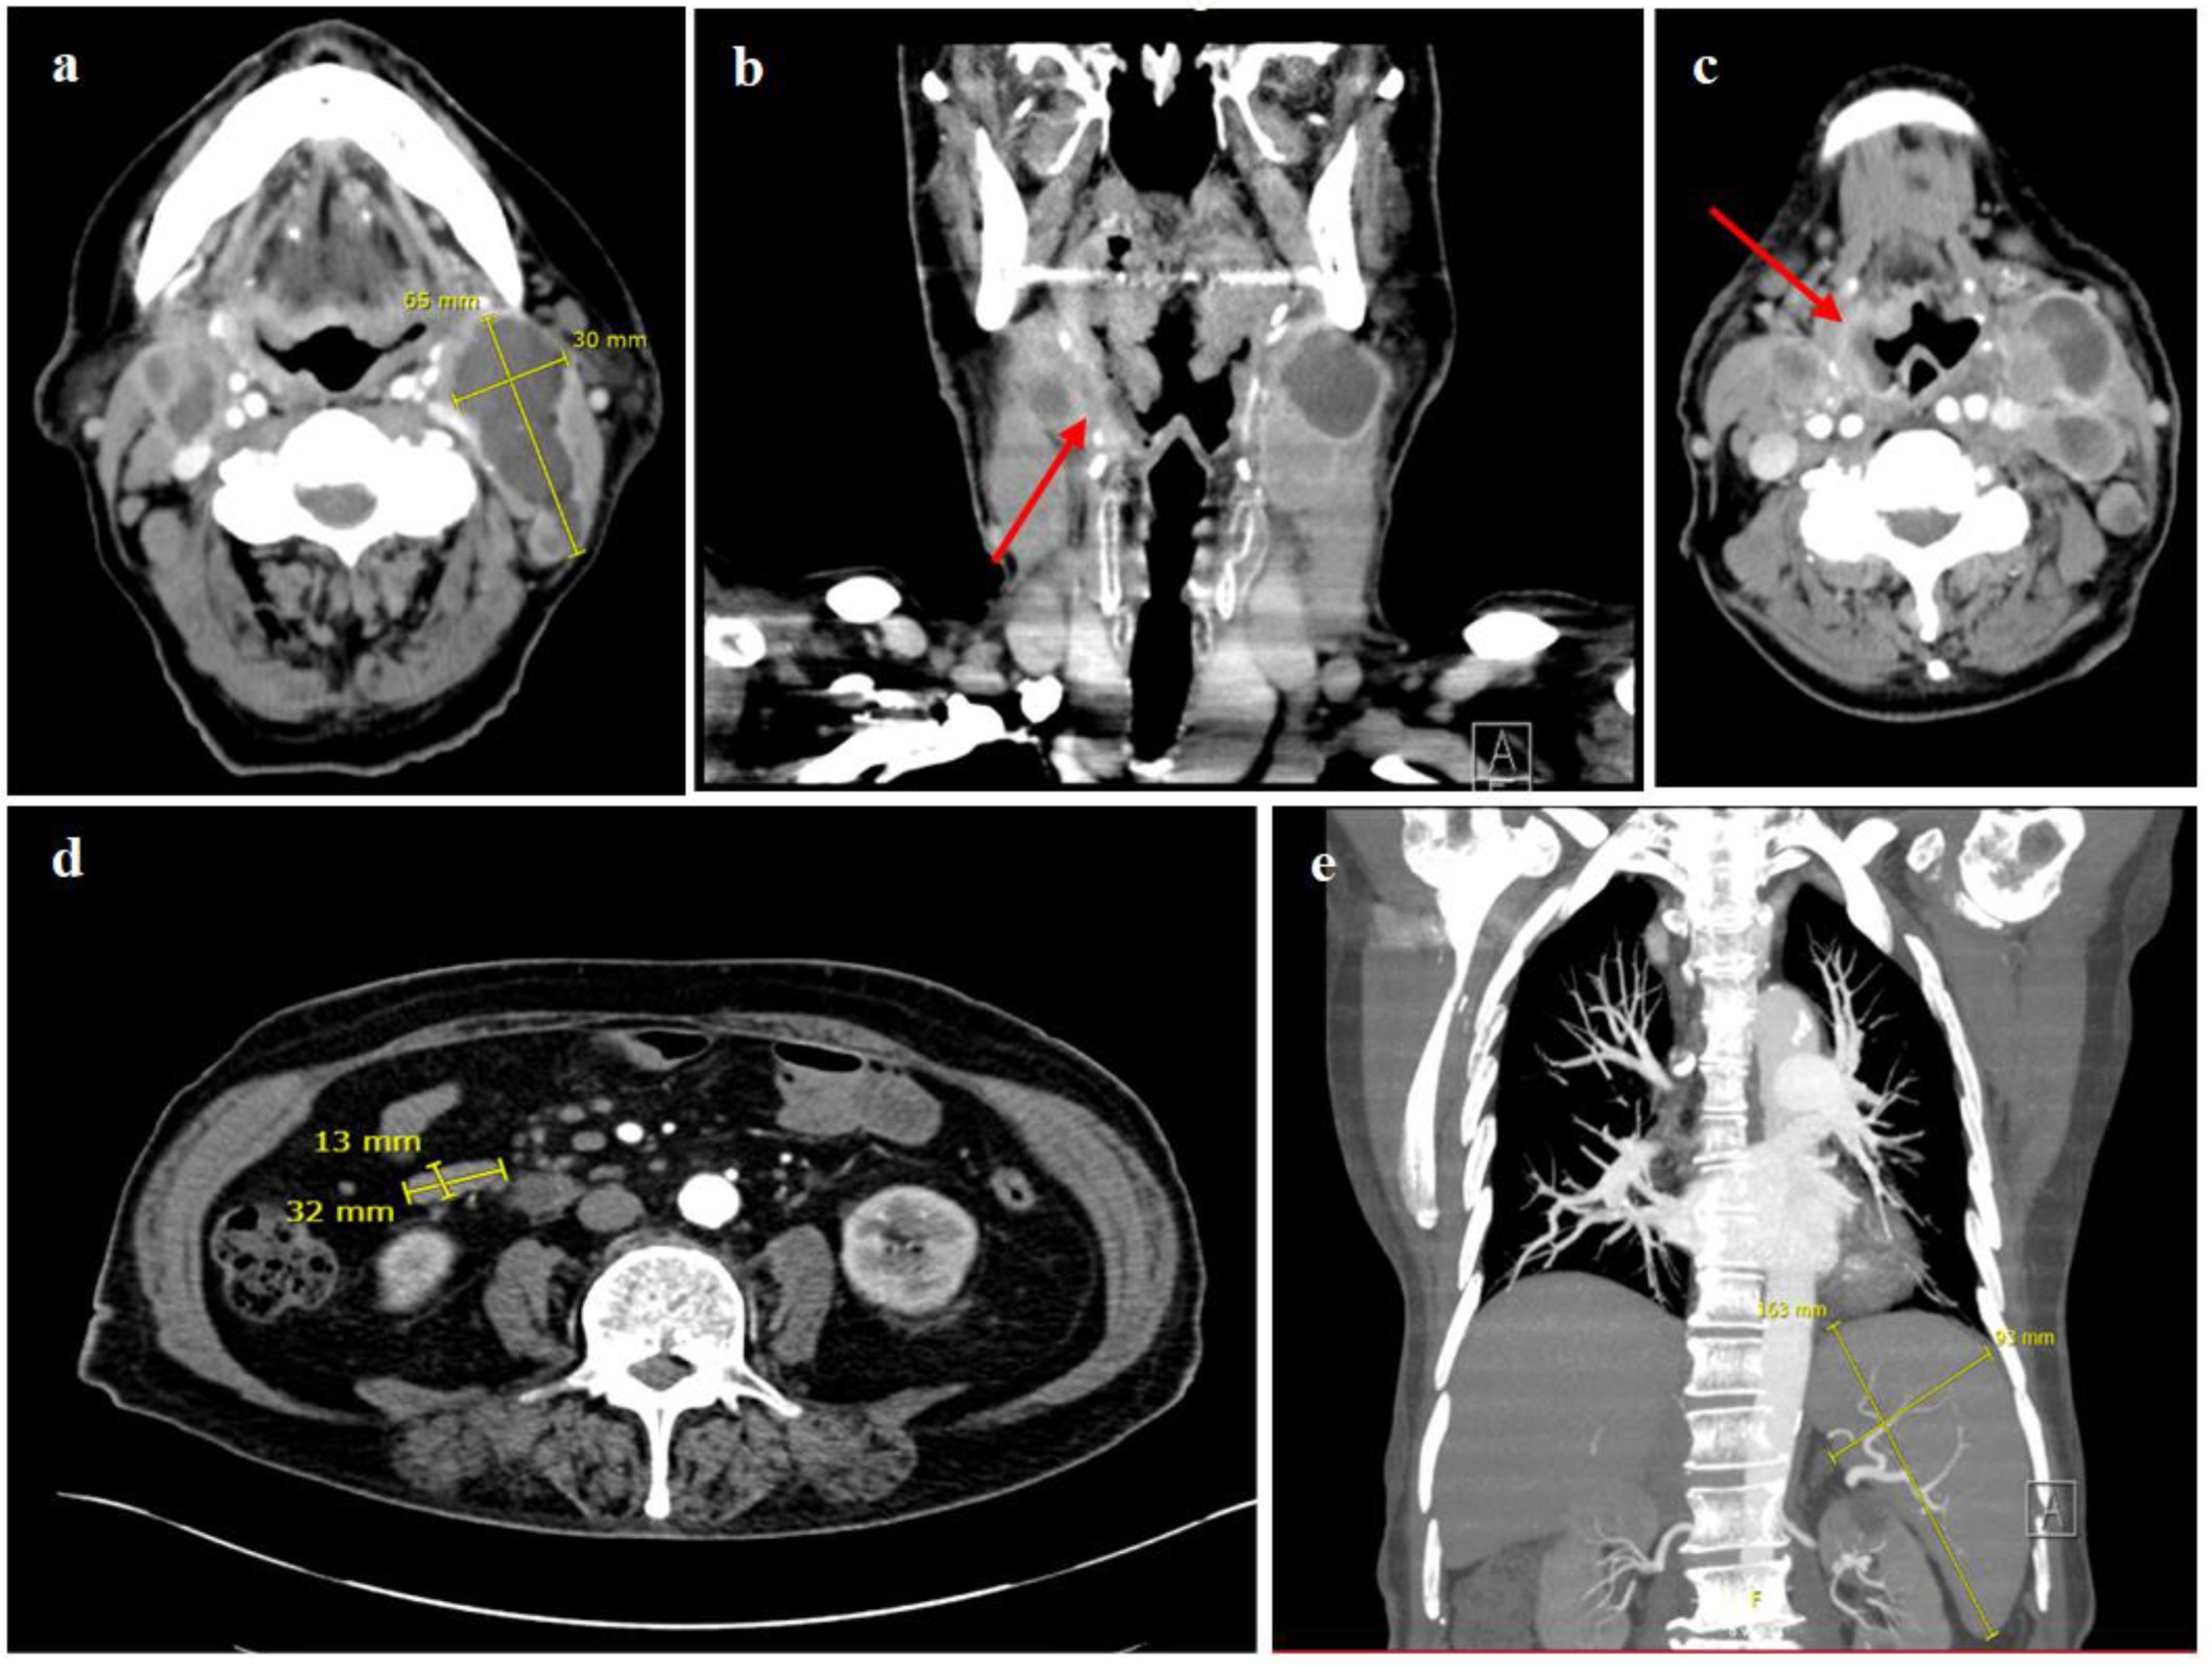

2. Case Report